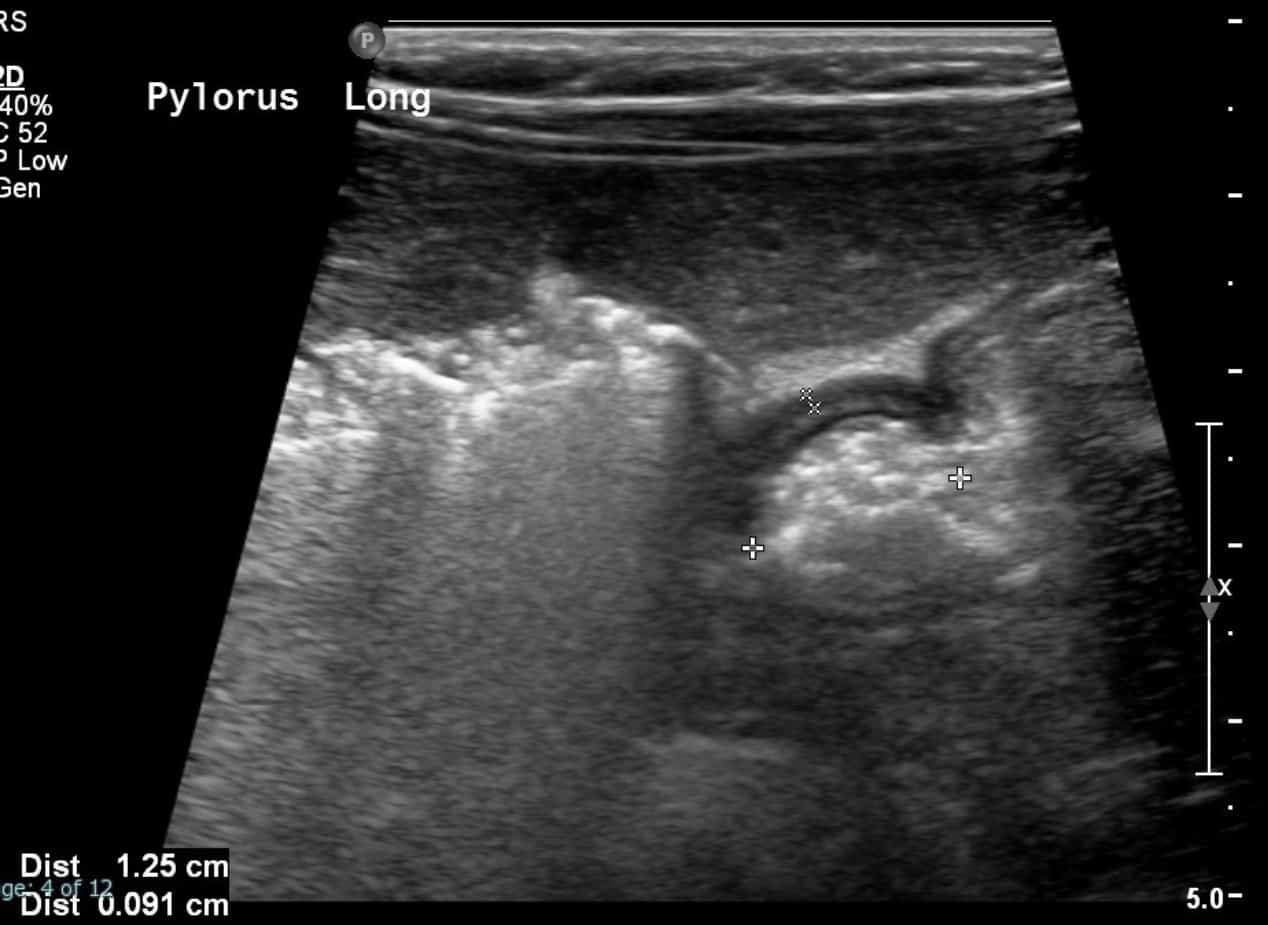

From medicine.uams.edu

Pyloric Stenosis UAMS Department of Radiology How Often Does A Baby Vomit With Pyloric Stenosis This is because of swelling of the surgical site of the pyloric muscle. In some cases, first symptoms can take up to two. The first symptom is usually vomiting. The vomiting is often described as non bilious and projectile vomiting, because it is more forceful than the usual spit ups commonly seen at this age. The signature symptom of pyloric. How Often Does A Baby Vomit With Pyloric Stenosis.